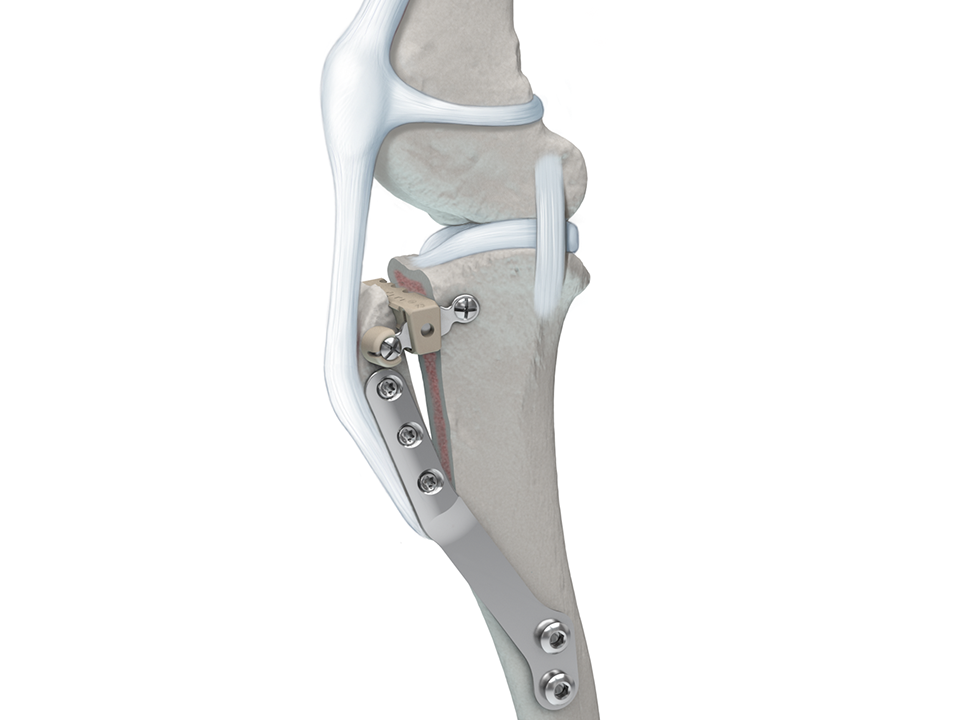

Unlike the TPLO, which relies on a reduction of the tibial plateau slope via a radial osteotomy, neutralization of the CrTT with the TTA is achieved by advancing the tibial tuberosity until the angle between the straight patellar ligament and the tibial plateau remains 90 or less, regardless of the stifle joint flexion/extension angle. The advancement of the tibial tuberosity is allowed by creating an osteotomy of the tibial crest in the frontal plane followed by plate stabilization after placement of a wedge within the osteotomy to maintain the gap width. A bone graft is placed within the osteotomy gap to enhance healing. Furthermore, the TTA can be used to treat CrCL rupture cases with concomitant medial patellar luxation (MPL) via the use of offset spacers that induce a lateral transposition of the tibial crest.

The TTA system (Fig 1) is indicated for the treatment of CrCL disease in canines. It is compatible with small and mini fragment systems and the plate is available in right and left versions as well as in the following sizes:

The locking screw trajectories in the proximal plate section are designed to optimize screw purchase within the tibial crest. Furthermore, the incorporation of locking technology (Fig 2) permits a fixed-angle device to increase construct stability.

Wedges and spacers are made of radiolucent PEEK (Fig 3). The Wedges are available in 8 widths (4.5, 6, 7.5, 9, 10.5, 12, 13.5 and 15 mm) and can easily be cut to the desired length to accommodate the tibial width using the graduated length markings. Additionally, 3 or 5 mm PEEK offset spacers may be snapped to the wedge allowing for simultaneous treatment of MPL (Fig 4).